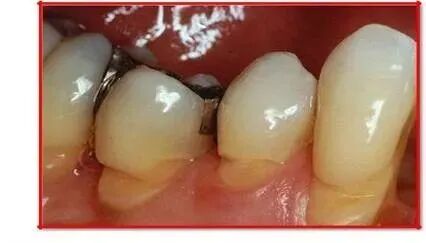

女,55 岁,每天用力刷牙。右侧近期出现酸软。可见牙齿表面整齐、坚硬、光滑的楔状缺损。这属于中度损伤,需要垫底以保护牙髓,再充填。

女,34岁。由于她特别喜欢使用硬毛牙刷、用力横刷,这样长期采用拉锯式横刷牙的方式,牙齿表面形成楔状缺损。她已经较严重,引起牙髓炎了,需要根管治疗以后再充填修补。